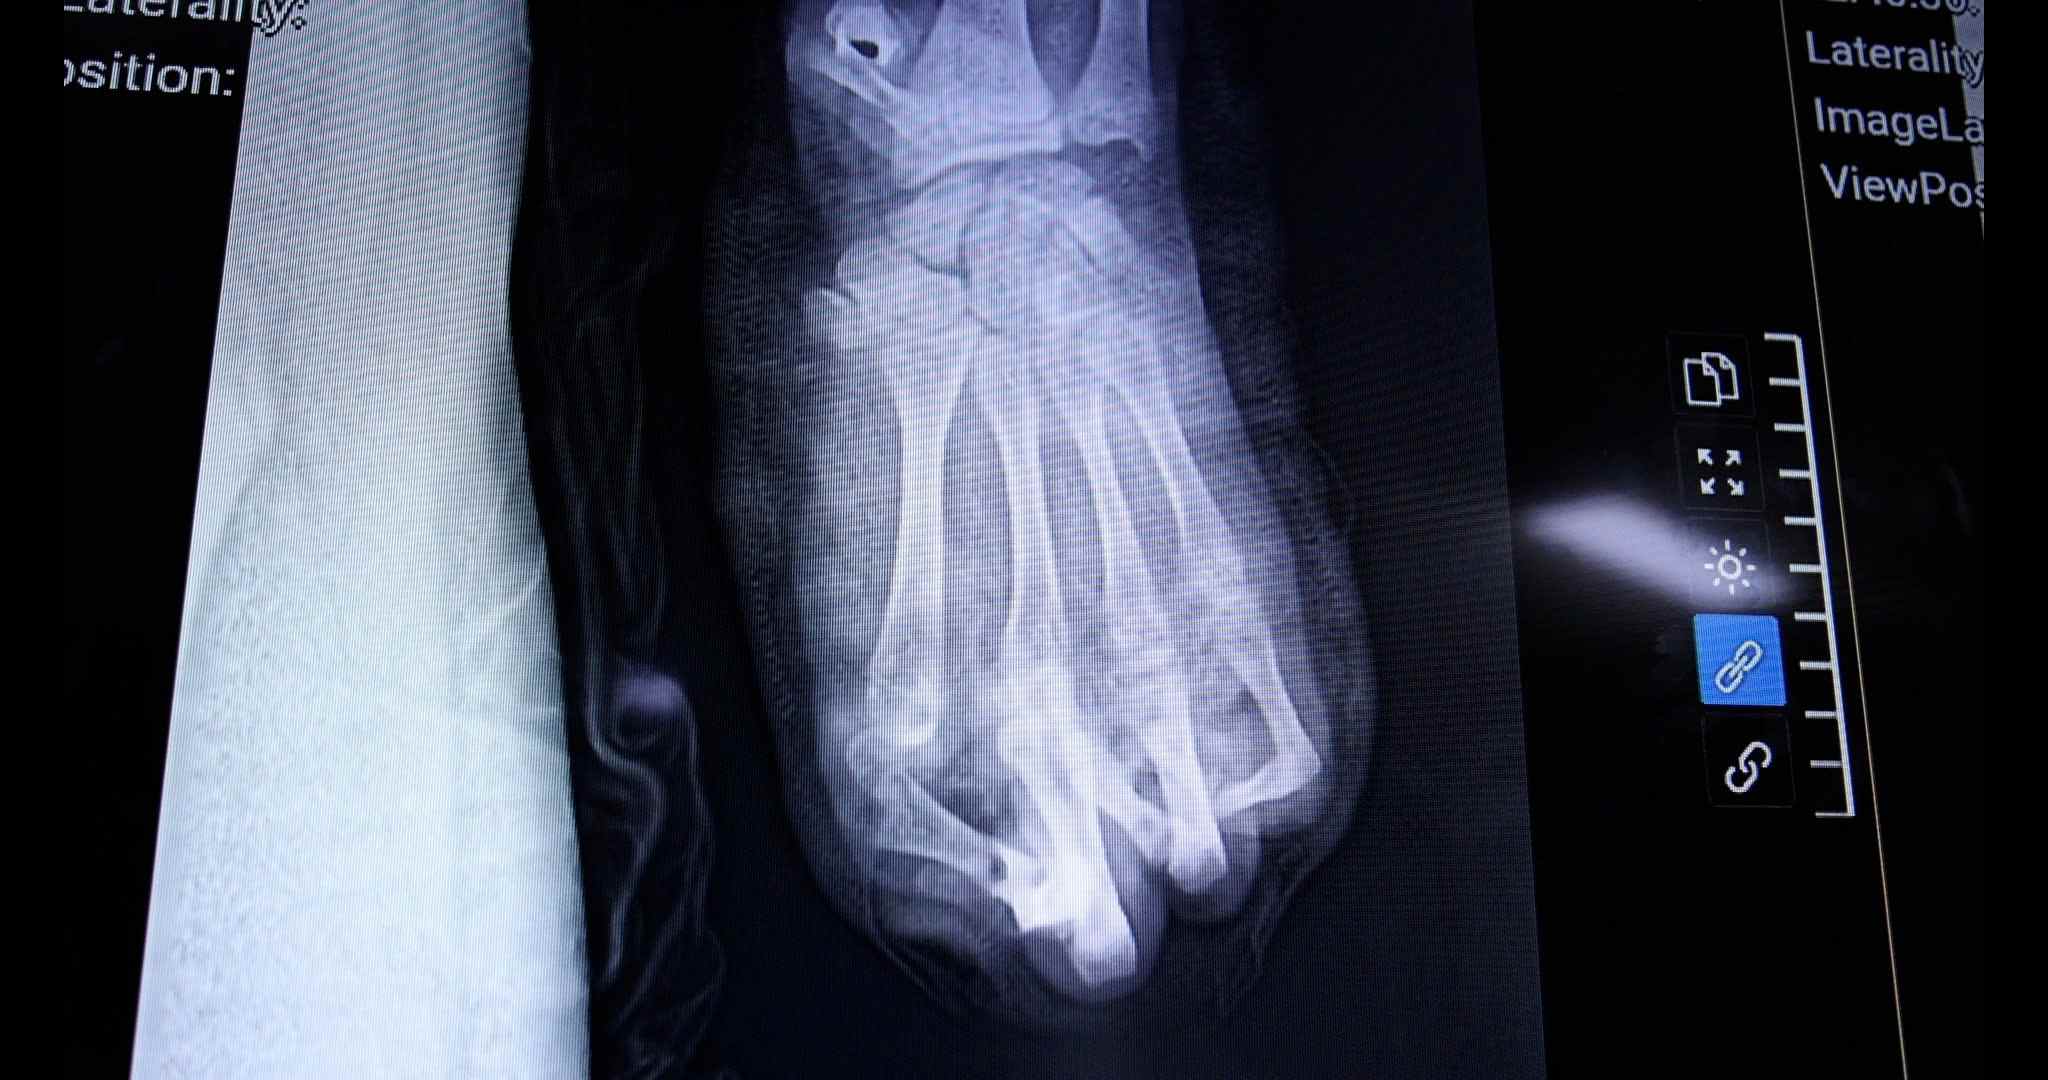

Hình ảnh bàn tay bị cụt do pháo nổ. Ảnh: BVCC.

Theo các bác sĩ, bàn tay trái của bệnh nhân bị dập nát gần như hoàn toàn, kèm theo vết thương phần mềm vùng đùi trái. TS.BS Nguyễn Quang Vịnh – Khoa Phẫu thuật Chi trên và Vi phẫu cho biết, đây là một trong những trường hợp tổn thương nặng nề, điển hình do pháo nổ gây ra.

Dù được cấp cứu và phẫu thuật khẩn trương, sau nhiều nỗ lực, ê-kíp điều trị chỉ có thể giữ lại 2 trong số 5 ngón tay cho người bệnh. Toàn bộ vùng gan tay và cổ tay bị dập nát nặng, khiến quá trình điều trị dự kiến kéo dài với nhiều cuộc phẫu thuật tiếp theo. Tiên lượng lâu dài, bệnh nhân có thể chỉ phục hồi được một phần chức năng rất hạn chế của bàn tay trái.

Hiện người bệnh đã được cắt lọc tổ chức dập nát, lấy bỏ các dị vật là mảnh pháo. Trong thời gian tới, các bác sĩ sẽ tiếp tục che phủ vùng hoại tử bằng vạt da và dự kiến sau vài tháng sẽ phẫu thuật chuyển ngón chân lên thay thế cho ngón tay cái đã mất. Tuy nhiên, dù thuận lợi, bệnh nhân vẫn phải chấp nhận mất ít nhất 2 ngón tay vĩnh viễn.